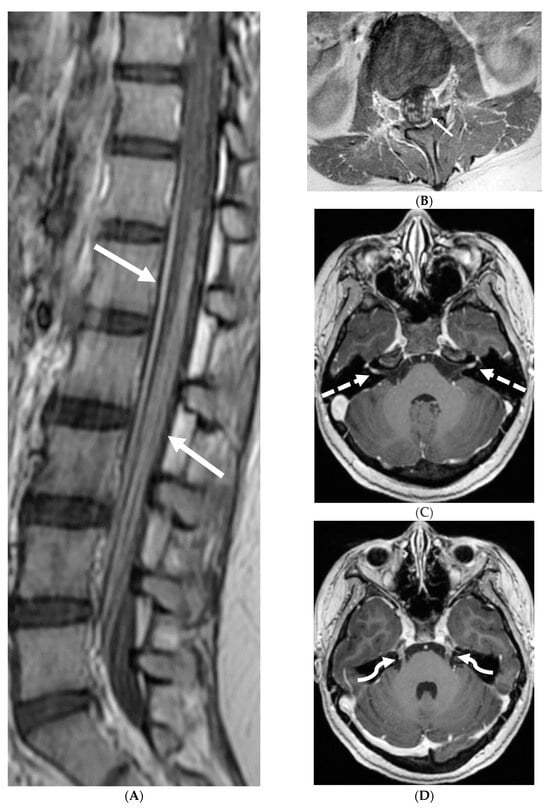

Marked focal nodularity and mass effect causing a deformed contour on the spinal cord favor a neoplastic process (Figure 7) [62]. Accurate staging is crucial as the presence of leptomeningeal or multifocal disease have implications on radiotherapy fields and total dose. Additionally, PET-CT scan assists in evaluating for an extracranial primary site [63].

Figure 7.

3-year-old boy with 2 weeks history of headache and vomiting. Axial FLAIR (A), post contrast axial T1 FS (B) and sagittal 3D inversion recovery (C) images demonstrate FLAIR hyperintensity in the interpedencular cistern (curved arrow) and mild hydrocephalus. Extensive meningeal enhancement most prominent at the skull base, basal cisterns, and Sylvain fissures (arrows), but extending throughout the brain. There is meningeal enhancement, with coating of the brainstem extends inferiorly along the cervical spinal cord (dashed arrows). Sagittal T2 (D), sagittal T1 (E) and fat saturated T1 post (F) images show extensive leptomeningeal with predominantly solid and some cystic nodules (curved arrows) on T2 sequence and isointense on T1 (arrows). Lesions predominantly involve the posterior spinal canal, causing mass effect and anterior displacement of the spinal cord. The solid nodules show enhancement after contrast injection and extensive uniform diffuse LME around the cord (dashed arrows). Pathology: Primary Meningeal Rhabdomyosarcoma.